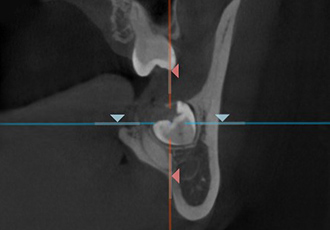

CT検査によって取得した口腔内の3Dデータから、歯の位置や埋伏歯(歯冠の全てまたは一部が埋まって出ていない歯)・過剰歯(決まった本数よりも多く生えている歯)などを確認します。

これらを事前に確認しておくことで、歯が移動する際に邪魔になってしまうのを防ぎます。また、歯の移動に大きく関係する骨の厚さなどの情報も得られ、精度の高い矯正治療のために不可欠な検査です。

CT検査を行うことで、さまざまな角度の断面から

歯の位置や方向を確認することができます。

アキシャル像

コロナル像

サジタル像

※症例に合わせて必要な場合にのみCT検査を行います。